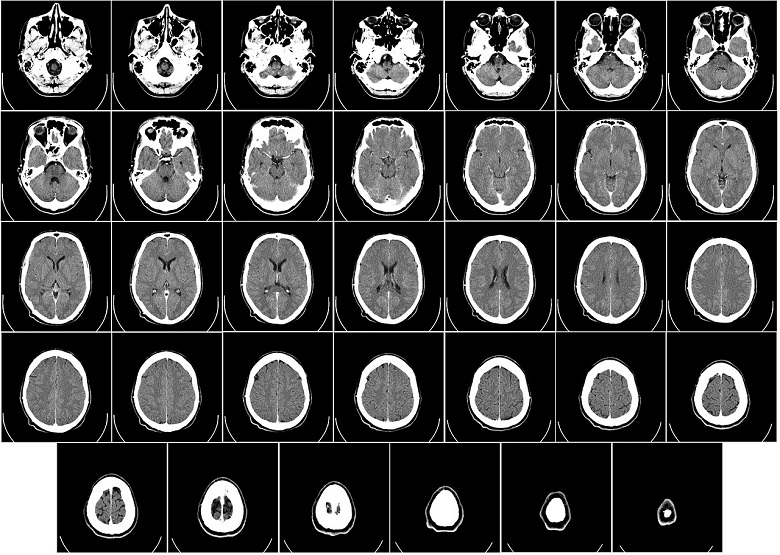

O diagnóstico é feito após avaliação médica com realização do exame físico geral e neurológico, com identificação dos sintomas, seguida da avaliação dos exames complementares, normalmente tomografia computadorizada e ressonância magnética com contraste, que evidenciam detalhadamente a localização e podem orientar o médico em relação ao tipo de tumor.